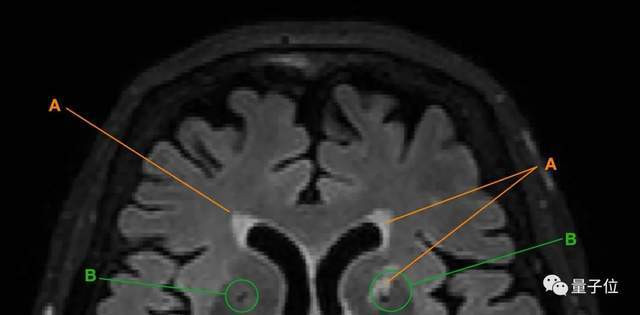

得出以上结论,研究人员主要是通过追踪老人大脑中脑白质高信号(WMH)和腔隙的变化来实现的。

△A为脑白质高信号;B为腔隙

以上两种现象都是脑小血管病(CSVD)的主要表现。

这种疾病在老年人群体中高发,会表现出情感障碍、认知功能下降等症状,

也就是说,当老人的大脑中出现脑白质高信号、腔隙变多变大等情况,就意味着老人的大脑可能在发生退化。